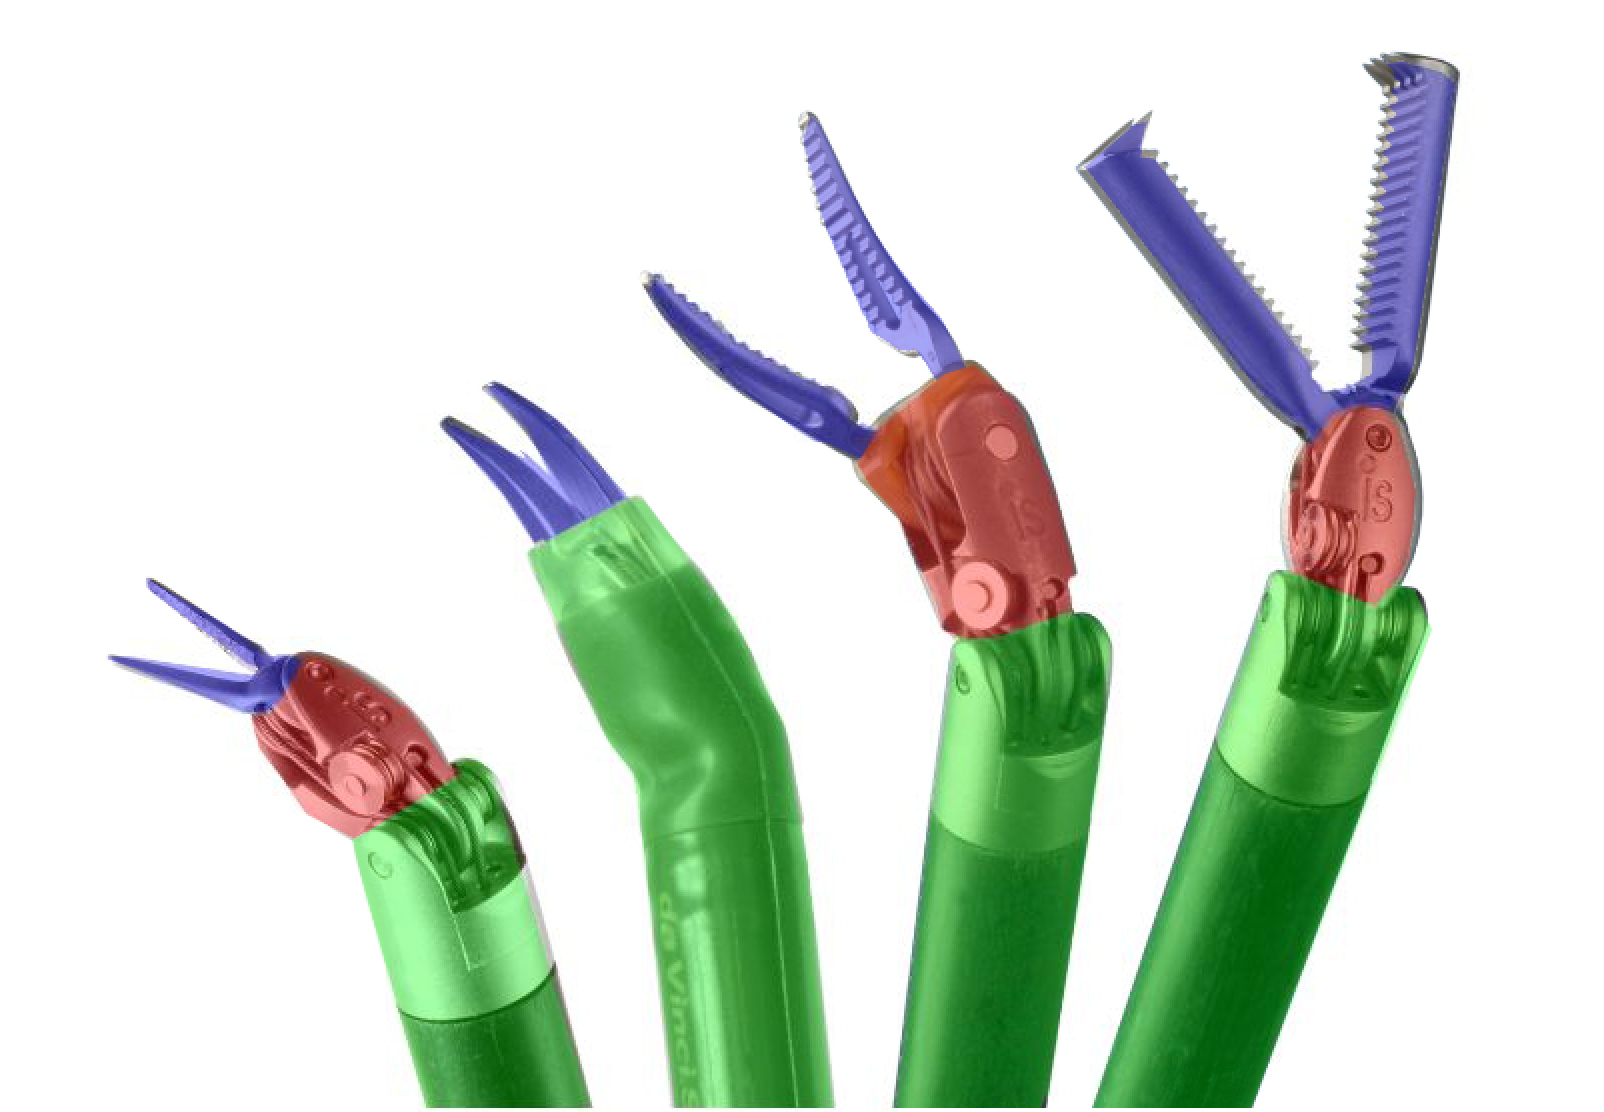

Our challenge was made up of 3 sub-problems. The first was binary instrument segmentation, where each frame was separated into da Vinci Xi instruments and a background class, which contained an ultrasound probe, surgical clips and porcine tissues. The second task was instrument part segmentation, where we scored the participants on whether they could correctly segment each articulating part of the instrument (see Fig. 3). Our final task was to segment and classify the instruments (see Fig. 4).

We provided the first 225 frames of 8 sequences as training data and kept the last 75 frames of those 8 sequences as test data. 2 of the full 300 frame sequences were kept as test sequences. Test labels were kept hidden from the participants. Our datasets contain 7 different robotic surgical instruments. The Large Needle Driver, Prograsp Forceps, Monopolar Curved Scissors, Cadiere Forceps, Bipolar Forceps, Vessel Sealer and additionally a drop-in ultrasound probe, which is typically held in the jaws of the Prograsp Forceps instrument. Samples from the training datasets are depicted in Fig. 2 and examples of the different instrument types are shown in Figure 3 and 4.

IV-D Type Segmentation

The final challenge was to identify each instrument type from the list of Large Needle Driver, Prograsp Forceps, Monopolar Curved Scissors, Vessel Sealer, Fenestrated Bipolar Forceps and Grasping Retractor (see Fig. 4). Only 6 teams participated in this challenge, due particularly to the significant increase in difficulty in recognizing many of the da Vinci instruments from one another.